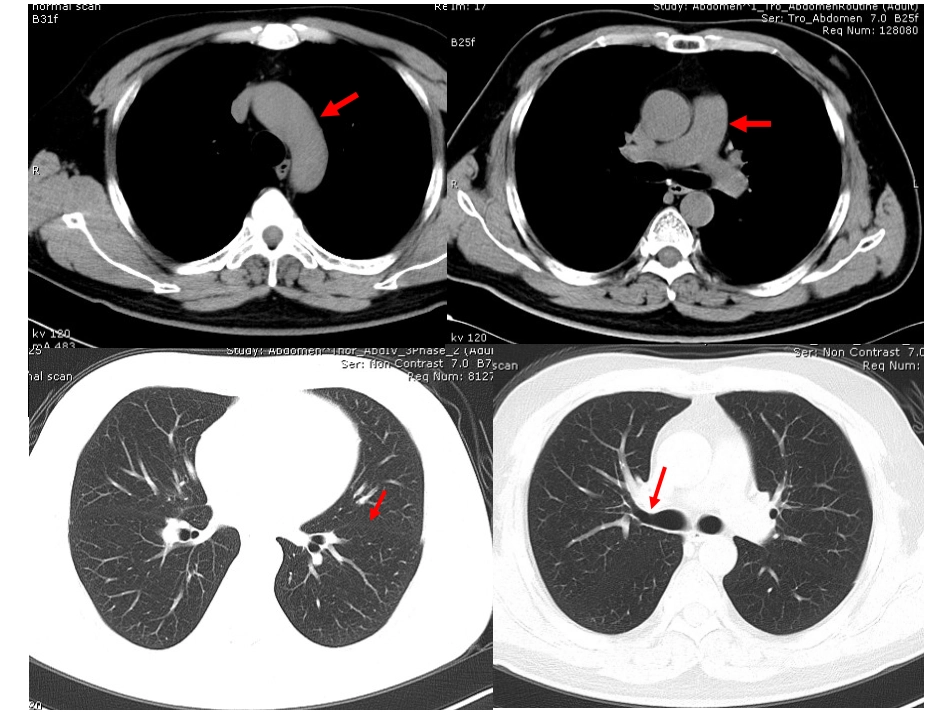

影像学考试试题